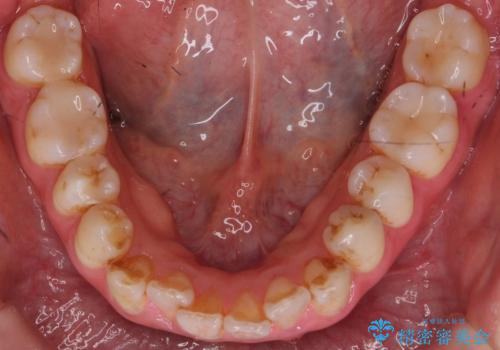

歯科衛生士によるPMTCでお口のケア

- 歯医者に来院することが久しぶりで、まずはクリーニングを希望とのことでした。コースや内容は、一番状態に合ったものでとのことだったため、PMTC60分コースを行いました。

審美的面だけではなく、歯周病や虫歯・口臭などのリスクを予防することができます。

汚れを除去することにより、症状の早期発見につながります。